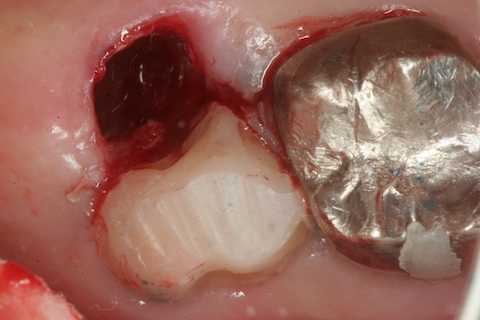

今日の抜歯再植術シリーズ39.2 2025.11.15